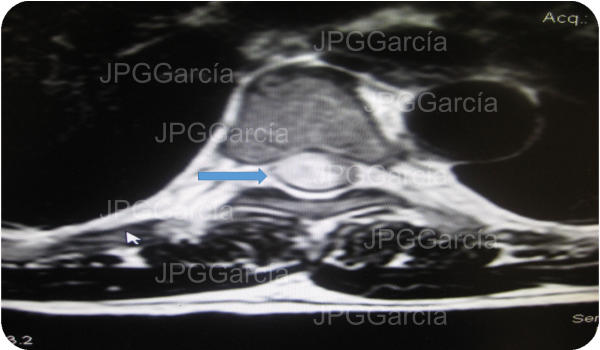

Estudio de resonancia magnética prequirúrgico que demuestra

una lesión tumoral torácica relacionada a un meningioma

RESECCIÓN MICROQUIRÚRGICA DE MENINGIOMA TORÁCICO

Estudio de resonancia magnética prequirúrgico que demuestra una lesión tumoral torácica relacionada a un meningioma